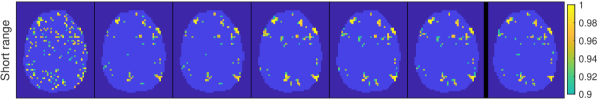

4.1 Simulated data

We consider a simulated dataset that is randomly generated using the anisotropic Matérn (A-M) prior with fixed hyperparameters. The size and shape of the brain is taken from the word object dataset, described below. We first simulate four different 3D fields of activity coefficients ) using four A-M priors with different hyperparameters. We select the hyperparameters to highlight different spatial characteristics and name the four composed conditions: Weak (Small activation magnitude, low ), Short range (Short spatial range ), Long range (Long spatial range ) and Anisotropic ( and ). A summary of the selected hyperparameters can be seen in Table 2, and one slice of the activity coefficient maps are shown in Fig. 1.